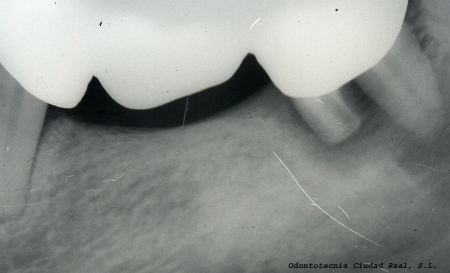

En nuestro laboratorio de prótesis dental no solo nos preocupamos de la perfecta armonía visual - estética de los casos que nos son confiados, sino además estamos en permanente comunicación con nuestros clínicos, con el fin de lograr una óptima función al finalizar los tratamientos.

Producto de esa colaboración y constante comunicación, sumado al estudio minucioso de cada caso y la utilización de equipamientos de alta tecnología hacen que nuestros servicios marquen la diferencia y que mantengamos esa inquietud de querer seguir brindando lo mejor.